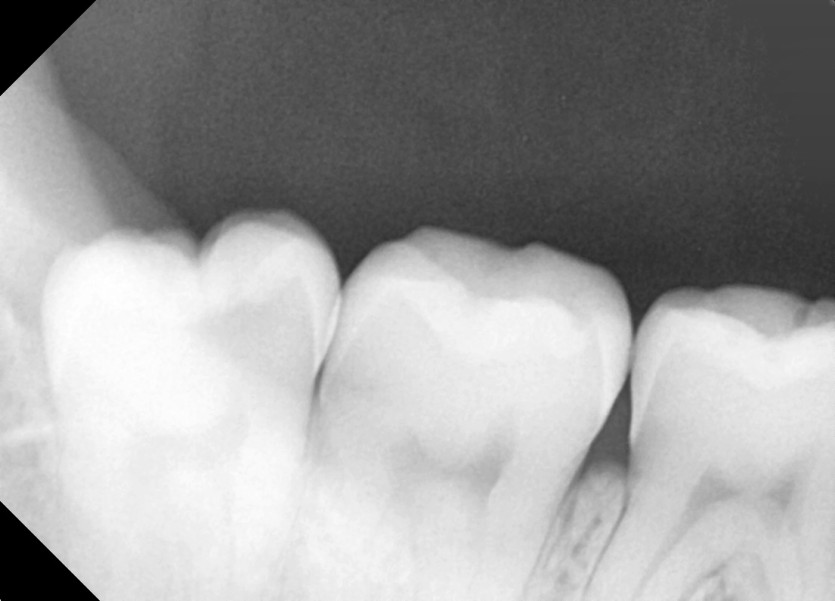

#48 사랑니 발치

구강 외과 전문의가 당일 발치했습니다.